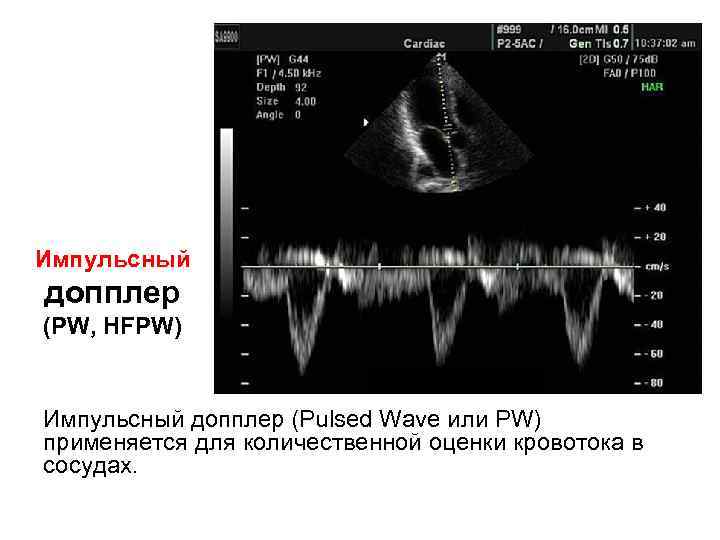

Импульсный допплер (PW, HFPW) Импульсный допплер (Pulsed Wave или PW) применяется для количественной оценки кровотока в сосудах.

Импульсный допплер (PW, HFPW) Импульсный допплер (Pulsed Wave или PW) применяется для количественной оценки кровотока в сосудах.

Импульсный допплер (PW, HFPW) • • На временной развертке по вертикали отображается скорость потока в исследуемой точке. Потоки, которые двигаются к датчику отображаются выше базовой линии, обратный кровоток (от датчика) - ниже.

Импульсный допплер (PW, HFPW) • • На временной развертке по вертикали отображается скорость потока в исследуемой точке. Потоки, которые двигаются к датчику отображаются выше базовой линии, обратный кровоток (от датчика) - ниже.